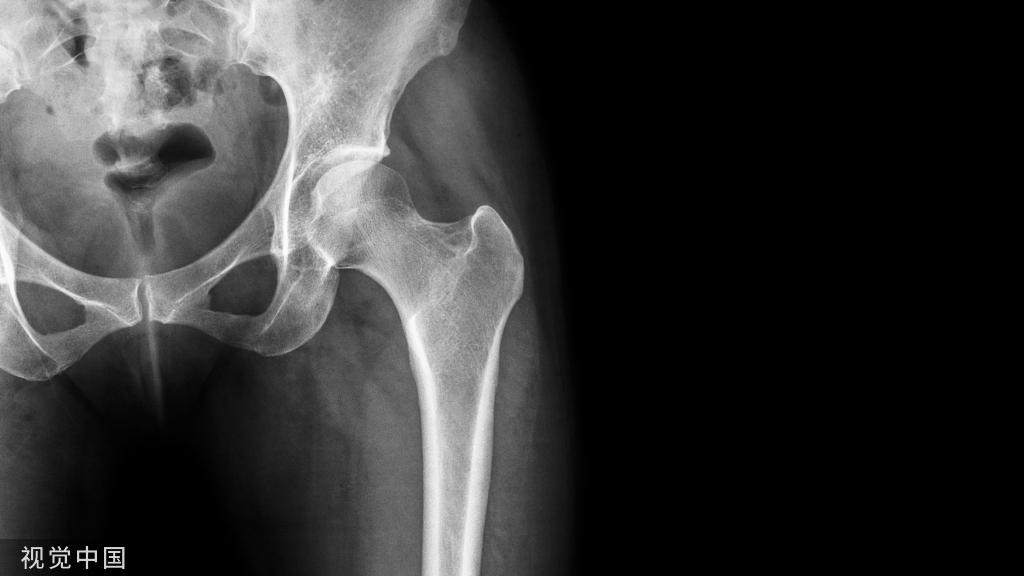

1、确定下肢关节的中心点(1)髋关节中心髋关节中心点由股骨头来确定,由于股骨头是相对比较规则的圆形,使用Mose圈或圆规就能确定股骨头中心也就是髋关节中心。